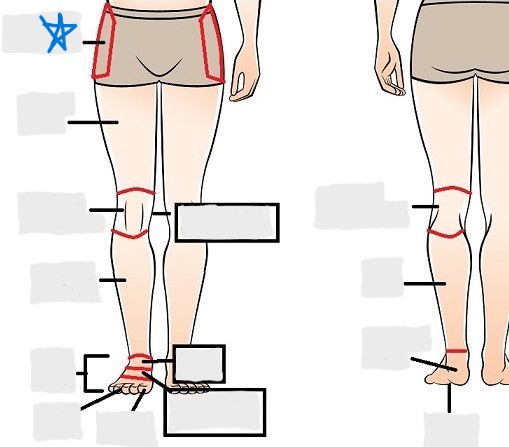

appendicular

coxal

femoral

patellar

popliteal

crural

sural

peroneal

calcaneal

plantar